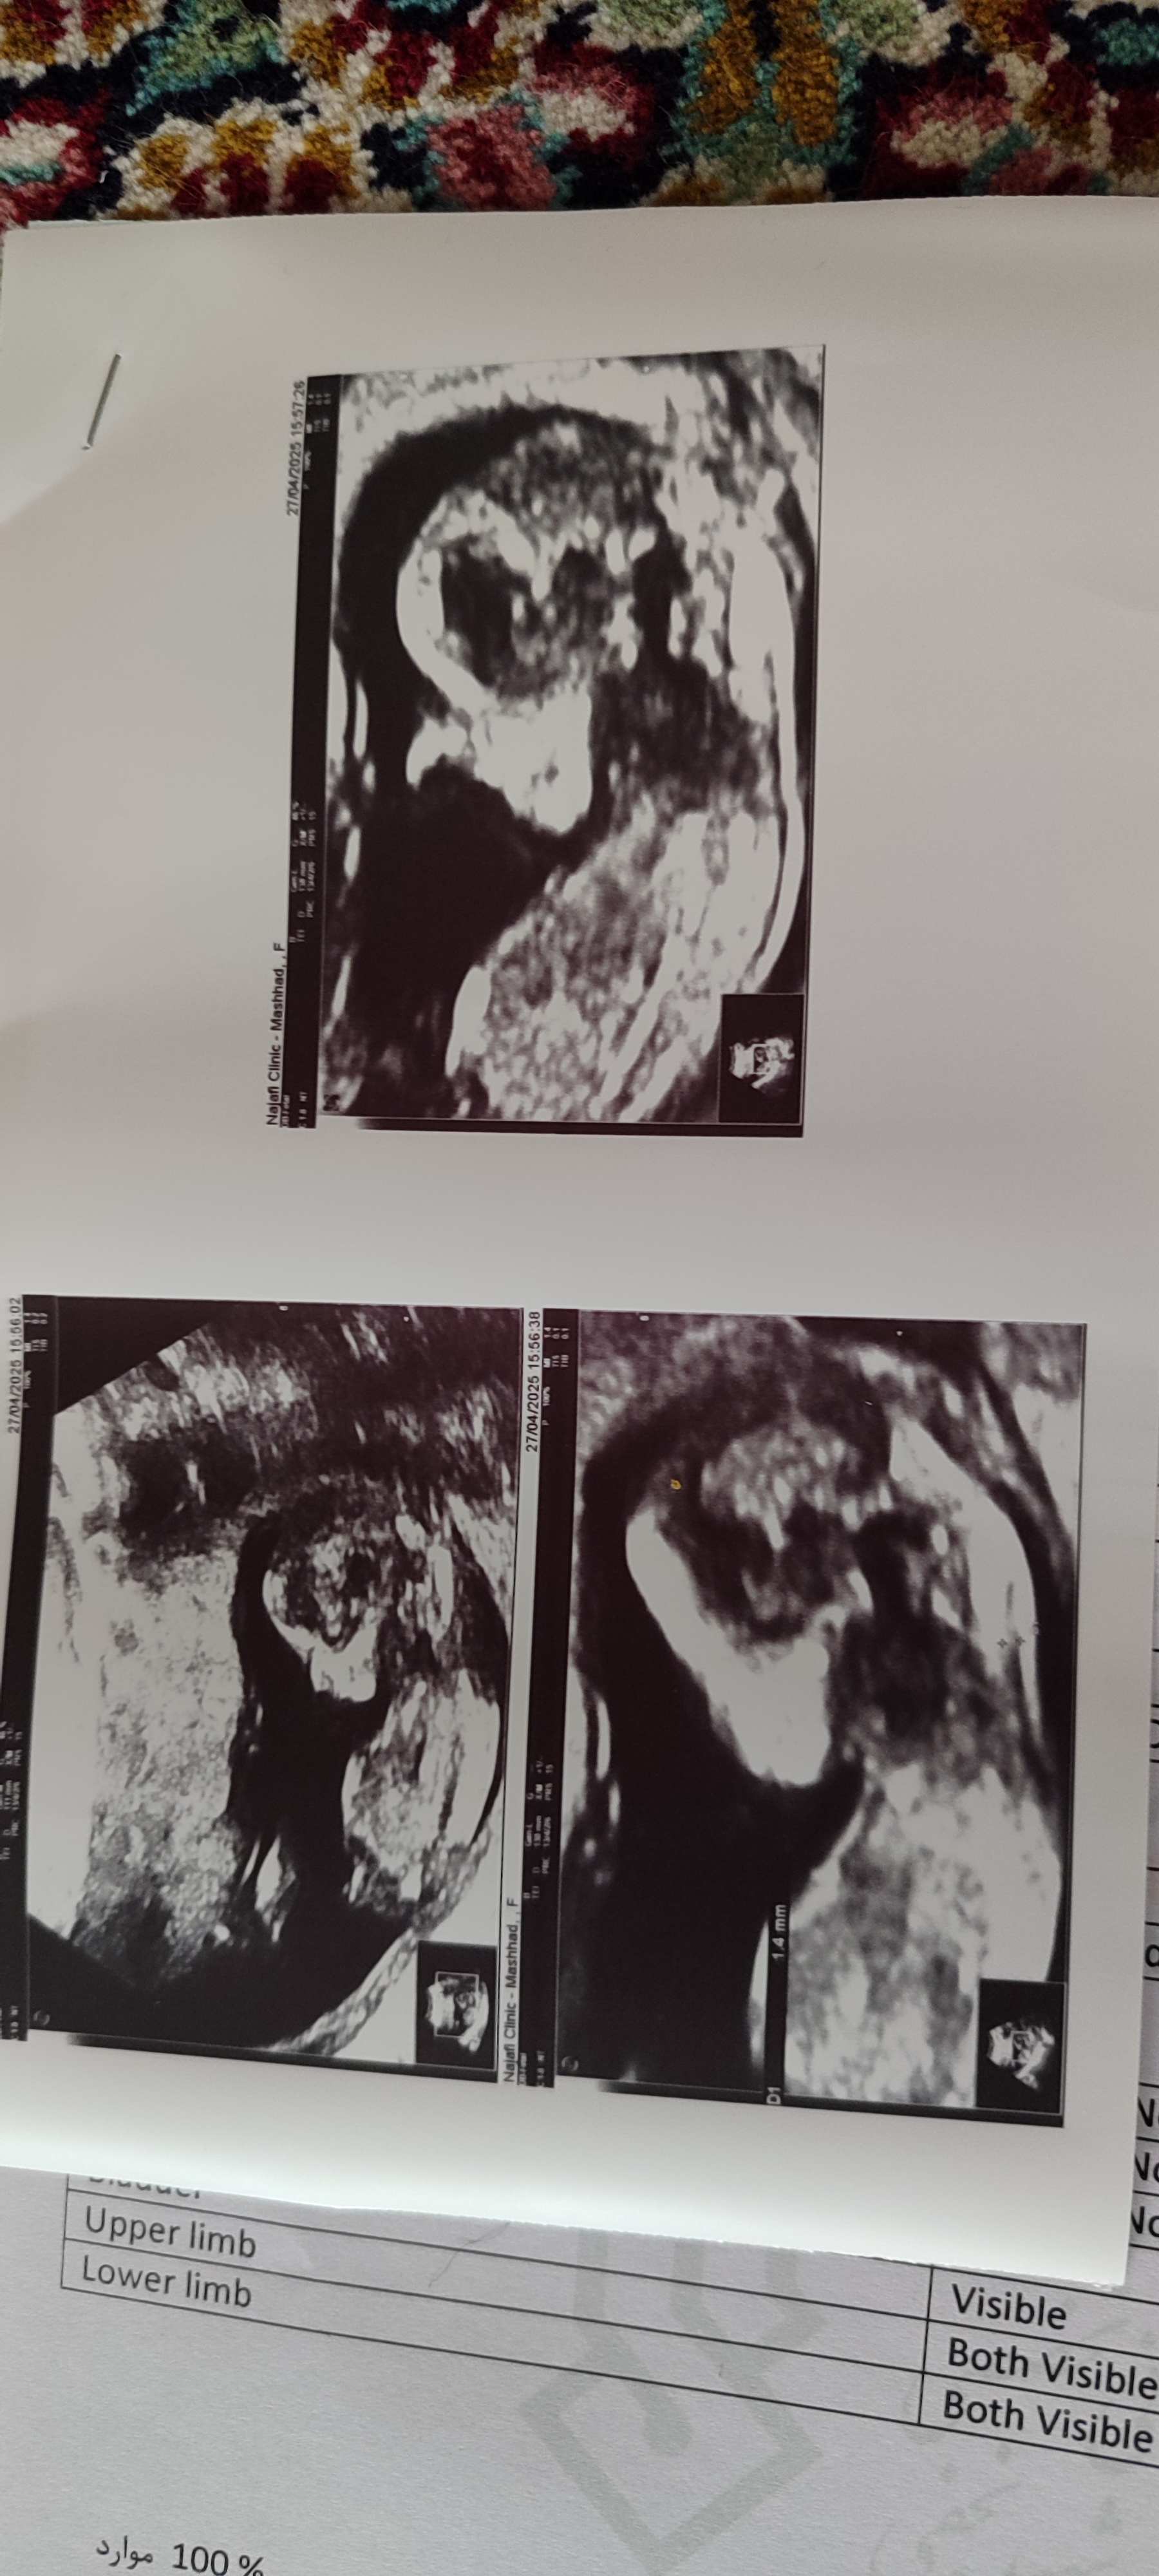

mamni_ayandeee مدیر استارتر عضویت: 1403/03/02 تعداد پست: 1192 عنوان بچه ها به نظرتون نی نی من چیه 33 بازدید | 1 پست فقط 6 هفته و 6 روز به تولد باقی مونده ! 1 5 10 15 20 25 30 35 40 1404/04/28 | 01:01 0 نفر لایک کرده اند ... گزارش تاپیک نامناسب